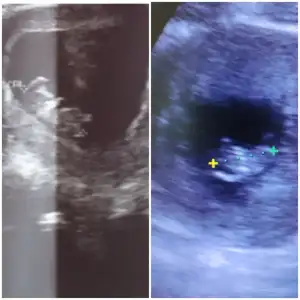

Evet ya o çok netmiş ne güzel ultrason diğerini niye garip bıraktın anasıTeşekkürler canımya kimi kız dedi kimi erkek arafta kaldı çocuk

cheatcpt de erkeğe benzetti oğlumun o haftadaki ultrasonu ile kıyasladım bayada benzio aslında sadece onunki cok kaliteliydi özel hastane de bu garibimin ultrasonu cok kötü

sol oglanın sağ mavi renk olan şuanki bebişimin

Ya o hastane kapandı diğer özellerde 2500 cok pahalı vermek istemiyorum 2 çocuk daha var onlara harcarım ihtiyaçlarına ultrason cok onemli gelmiyor şuan ilk çocuk olsa evet kesin giderdimEvet ya o çok netmiş ne güzel ultrason diğerini niye garip bıraktın anasıerkek diyorum ben ya